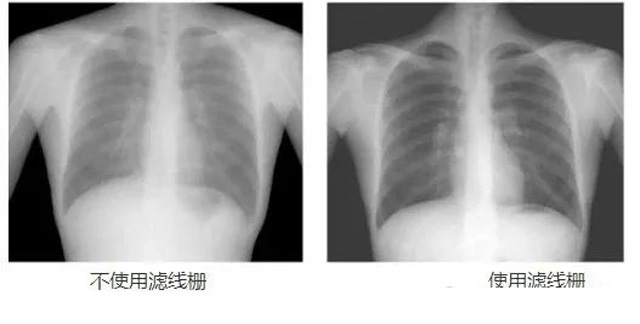

DR影像X射线在医学检查成像有着广泛的使用。但是它的散射线影响成像质量问题。滤线栅的发明使用很好的解决了这个问题,构造简单铅条粗,密度和栅比规格单一,能减散射线但吸收较多原发射线。伴随这医疗影像设备技术的发展,这个滤线栅的工艺制造技术有改进,铅条变薄,栅密度和栅比有更多的选择。特别是材料方面有新组合,填充物也依不同成像要求优化。特别是移动DR这类型的DR设备的出现,滤线栅也设计成立方便拆卸形的,方便使用。被照体情况决定是否使用,更好平衡成像质量与射线剂量。

焦距(f):断面看铅条延长线会聚点到栅板垂直距离,即栅板焦距(半径)。栅密度(N):每厘米范围内含有的铅条数,一般40~65线/cm。栅比(R):铅条高度与栅条间隙之比,比值越高滤除散射线能力越强,一般8:1~14:1之间。结构组成:3~5mm薄板,用0.05~0.1mm铅条,夹持在铝或纸之间平行或按斜率排列,相邻铅条间用易透X线物质填充定位、黏合,如木、纸、铝片等。

放置方面:置于人体与片盒间,聚焦面朝向X线入射方向,X线焦点放铅条会聚线上,不能反置,X线中心对准滤线栅中心,左右偏移不超3cm,倾斜X线管要与铅条排列方向平行。摄影时焦距改变不超焦距的25%;活动式滤线器运动时间至少长于曝光时间的1/5;因吸收原发射线要适当增加曝光条件;四肢薄位置一般不用滤线栅;不同千伏对应不同栅比;立位胸片架、乳腺DR摄影等有各自特定滤线栅要求。